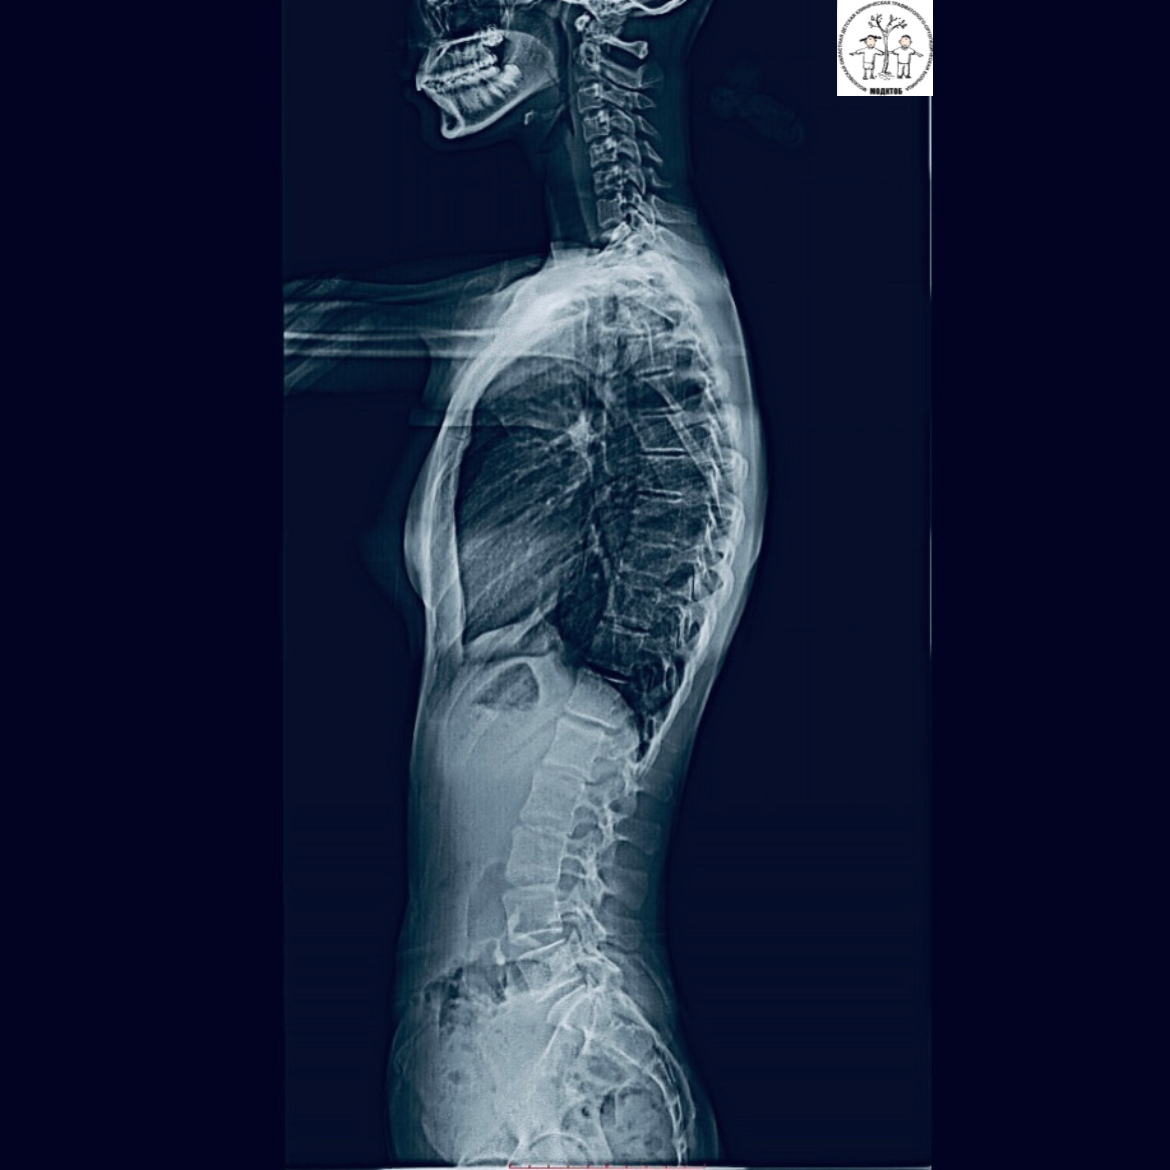

🔹Панорамная рентгенография — это современный метод диагностики, который обеспечивает высокую точность и скорость получения снимков, что позволяет нашим врачам ставить точные диагнозы и назначать оптимальное лечение. Цифровая рентген-сшивка имеет множество преимуществ: ✔️ высокое качество изображения, четкие и детализированные снимки; ✔️ минимальная доза облучения; ✔️высококвалифицированная диагностика костно-суставной системы у детей с травмами и различными патологиями опорно-двигательного аппарата различной этиологии. 💬 «Отделение лучевой диагностики МОДКТОБ – уникальное отделение, сотрудники которого работают в тесном сотрудничестве со всеми структурными подразделениями больницы. Сегодня невозможно представить травматологию и ортопедию без современных методов лучевой диагностики и цифрового анализа. С уверенностью могу сказать, что установленный аппарат ZEXIRA DREX-ZX80 CANON с функцией сшивки рентгенологических изображений — один из немногих в Московской области, имеющий данную в

🔹Панорамная рентгенография — это современный метод диагностики, который обеспечивает высокую точность и скорость получения снимков, что позволяет нашим врачам ставить точные диагнозы и назначать оптимальное лечение.

Цифровая рентген-сшивка имеет множество преимуществ:

✔️ высокое качество изображения, четкие и детализированные снимки;

✔️ минимальная доза облучения;

✔️высококвалифицированная диагностика костно-суставной системы у детей с травмами и различными патологиями опорно-двигательного аппарата различной этиологии.

💬 «Отделение лучевой диагностики МОДКТОБ – уникальное отделение, сотрудники которого работают в тесном сотрудничестве со всеми структурными подразделениями больницы. Сегодня невозможно представить травматологию и ортопедию без современных методов лучевой диагностики и цифрового анализа. С уверенностью могу сказать, что установленный аппарат ZEXIRA DREX-ZX80 CANON с функцией сшивки рентгенологических изображений — один из немногих в Московской области, имеющий данную возможностью выполнения», — прокомментировал заведующий отделением лучевой диагностики МОДКТОБ Фомченко Антон Александрович.